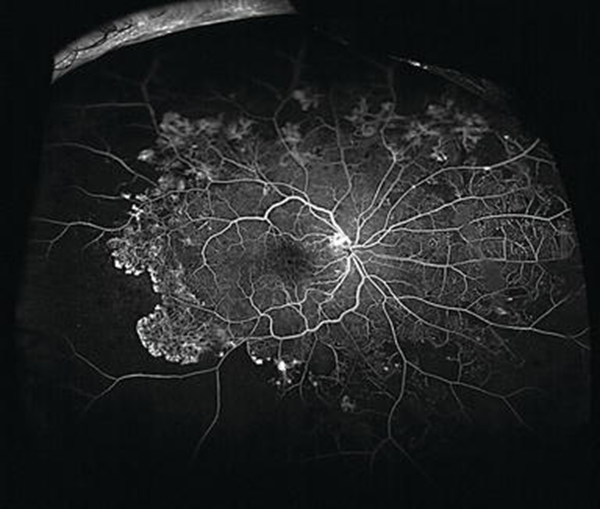

Η διαβητική αμφιβληστροειδοπάθεια είναι μία από τις συχνότερες αιτίες απώλειας όρασης παγκοσμίως. Οι επιστημονικές μελέτες έχουν δείξει πως η χρήση μηχανημάτων που επιτρέπουν τη λήψη εικόνων ευρέος πεδίου βοηθά στην ταχύτερη διάγνωση, τη σωστή σταδιοποίηση και την καλύτερη αντιμετώπιση ασθενών με Σακχαρώδη διαβήτη.

Το Eye Day Clinic στο πλαίσιο παροχής υψηλής ποιότητας υπηρεσιών υγείας προς τους ασθενείς του έχει στη διάθεση του το μηχάνημα τελευταίας τεχνολογίας Heidelberg Spectralis που επιτρέπει την απεικόνιση ευρέος πεδίου όχι μόνο σε ασθενείς που πάσχουν από διαβητική αμφιβληστροειδοπάθεια, αλλά και από άλλες παθήσεις του αμφιβληστροειδή και του χοριοειδή. Με τον τρόπο αυτό, είμαστε σε θέση να παρέχουμε στους ασθενείς μας ταχύτερη και ακριβέστερη διάγνωση, αποτελεσματική παρακολούθηση και τη βέλτιστη δυνατή θεραπεία.